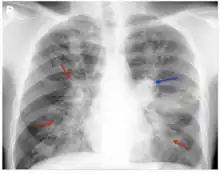

| The chest radiograph of an allergic bronchopulmonary aspergillosis patient shown with left-sided perihilar opacity (blue arrow) along with non-homogeneous infiltrates (transient pulmonary infiltrates indicated by red arrows) in all zones of both lung fields. | |